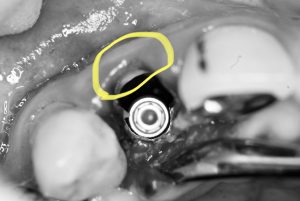

オペ途中に『破折した歯牙の唇側(外側)の歯質が一部使えそう‼︎』と判断し、歯根の一部を意図的に残し、ソケットシールド/ルートメンブレンテクニックに切り替えたそうです(ーー;)

(黄色の歯根一部がそれです)